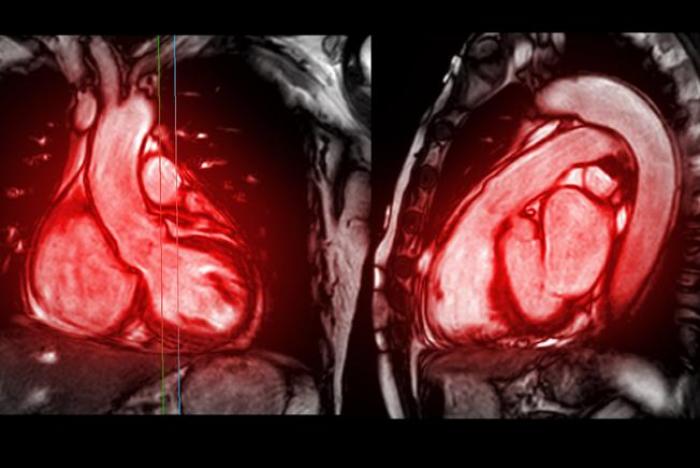

En los últimos años, la resonancia magnética cardíaca se ha consolidado como una técnica fundamental en el manejo de las enfermedades cardiovasculares. Este hecho hace que exista una demanda cada vez mayor de formación en una técnica de enorme utilidad en la práctica diaria. Si quieres profesionalizarte para llevar a cabo este tipo de atención clínica, debes aprovechar el curso que se te presenta a continuación.

El portal educativo de Emagister te propone realizar este curso Experto universitario en Aplicación clínica de la resonancia magnética cardíaca. Esta instrucción te brinda la posibilidad de desarrollar conceptos clave de medicina que sirvan de vehículo de comprensión de la medicina clínica, aprendes a determinar las principales enfermedades que afectan al cuerpo humano clasificadas por aparatos o sistemas, estructurando cada módulo en un esquema claro de fisiopatología, diagnóstico y tratamiento, además de saber cómo obtener métricas y herramientas para la gestión de la salud.